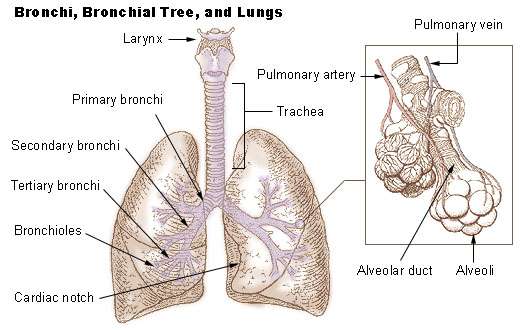

The respiratory tract is the path of air from the nose to the lungs. It is divided into two sections: Upper Respiratory Tract and the Lower Respiratory Tract. Included in the upper respiratory tract are the Nostrils, Nasal Cavities, Pharynx, Epiglottis, and the Larynx. The lower respiratory tract consists of the Trachea, Bronchi, Bronchioles, and the Lungs.

The trachea, which is also known as our windpipe, has ciliated cells and mucous secreting cells lining it, and is held open by C-shaped cartilage rings. One of its functions is similar to the larynx and nasal cavity, by way of protection from dust and other particles. The dust will adhere to the sticky mucous and the cilia helps propel it back up the trachea, to where it is either swallowed or coughed up. The mucociliary escalator extends from the top of the trachea all the way down to the bronchioles, which we will discuss later. Through the trachea, the air is now able to pass into the bronchi, bronchioles and finally alveoli before entering the pulmonary capillaries.

The lower respiratory tract starts with the larynx, and includes the trachea, the two bronchi that branch from the trachea, and the lungs themselves. This is where gas exchange actually takes place.

- Trachea

- Bronchi

The Passage Way From the Trachea to the Bronchioles

There is a point at the inferior portion of the trachea where it branches into two directions that form the right and left primary bronchus. This point is called the Carina which is the keel-like cartilage plate at the division point. We are now at the Bronchial Tree. It is named so because it has a series of respiratory tubes that branch off into smaller and smaller tubes as they run throughout the lungs.

Right and Left Lungs

The Right Primary Bronchus is the first portion we come to, it then branches off into the Lobar (secondary) Bronchi, Segmental (tertiary) Bronchi, then to the Bronchioles which have little cartilage and are lined by simple cuboidal epithelium (See fig. 1). The bronchi are lined by pseudostratified columnar epithelium. Objects will likely lodge here at the junction of the Carina and the Right Primary Bronchus because of the vertical structure. Items have a tendency to fall in it, where as the Left Primary Bronchus has more of a curve to it which would make it hard to have things lodge there.

The Left Primary Bronchus has the same setup as the right with the lobar, segmental bronchi and the bronchioles.

There are a number of terminal bronchioles connected to respiratory bronchioles which then advance into the alveolar ducts that then become alveolar sacs. Each bronchiole terminates in an elongated space enclosed by many air sacs called alveoli which are surrounded by blood capillaries. Present there as well, are Alveolar Macrophages, they ingest any microbes that reach the alveoli. The Pulmonary Alveoli are microscopic, which means they can only be seen through a microscope, membranous air sacs within the lungs. They are units of respiration and the site of gas exchange between the respiratory and circulatory systems.